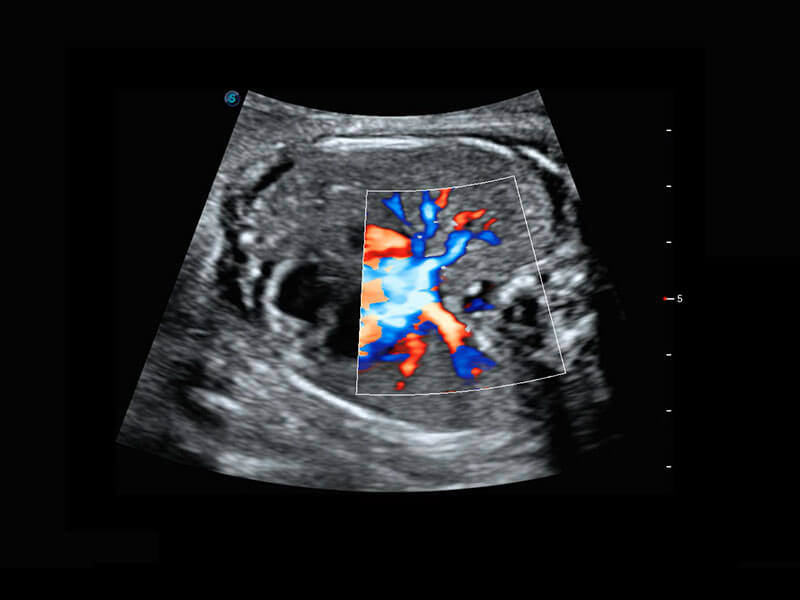

早孕筛查

P60在胎儿早孕期超声筛查中为您带来优异的图像质量。

• 早孕-胎心

• 高分辨率容积成像-早孕胎儿

• 胎儿体循环

• 光影成像-孕囊